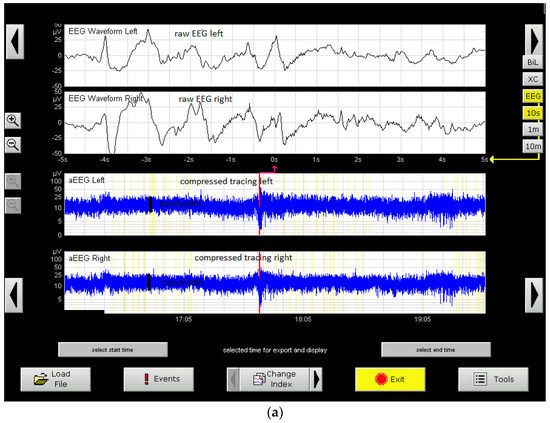

- Halberg, B.; Grossmann, K.; Bartocci, M.; Blenow, M. The prognostic value of early aEEG in asphyxiated infants undergoing systemic hypothermia treatment. Acta Paediatr. 2010, 99, 531–536. [Google Scholar] [CrossRef]

- Massaro, A.N.; Tsuchida, T.; Kadom, N.; El-Dib, M.; Glass, P.; Baumgart, S.; Chang, T. aEEG Evolution during Therapeutic Hypothermia and Prediction of NICU Outcome in Encephalopathic Neonates. Neonatology 2012, 102, 197–202. [Google Scholar] [CrossRef]

- Osredkar, D.; Toet, M.C.; van Rooij, L.G.M.; van Huffelen, A.C.; Groenendaal, F.; de Vries, L. Sleep–wake cycling on amplitude-integrated EEG infull-term newborns with hypoxic–ischemi encephalopathy. Pediatrics 2005, 115, 327–332. [Google Scholar] [CrossRef]